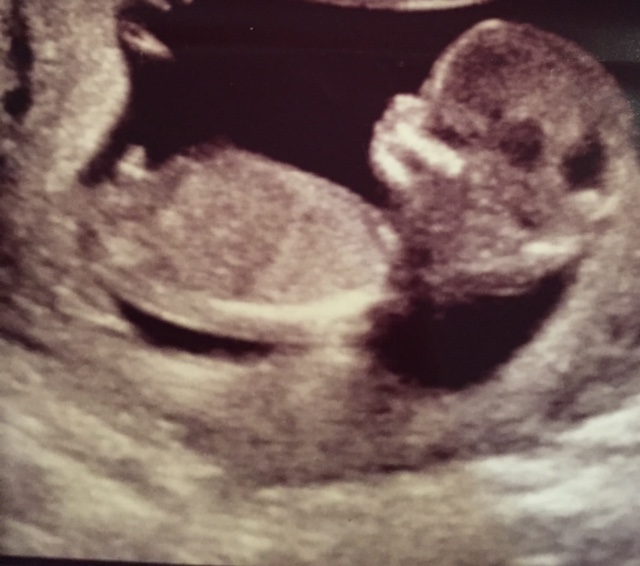

13 w, 1 d U/S - I see boy, would love guesses!

So my ultrasound tech would NOT budge on guessing boy or girl. But, I saw in between the legs what looked to be a pretty significant scrotum. No white lines of any kind. Then, we got these profile shots below. I said to her, "That's a penis." She just smiled. She wouldn't go back to the in-between-the legs shot for another glimpse. When I saw my OB and repeated my opinion, she said, "That's not a penis. It's too soon to tell either way." (She's very conservative about these things). But tell me that's not a little turtle head looking thing!

FYI: I have two boys who also had very similar skull shapes (box shape). I was swaying for girl, but I feel like this has depleted any hope of that.

The baby has its legs up in the air, as you can see in one of the pictures. Guesses please!